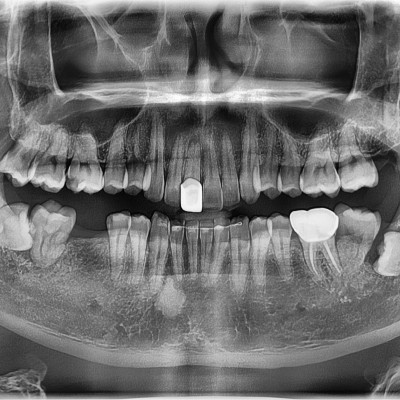

#18, 48 사랑니 발치 #18, 48 사랑니 발치 구강 외과 전문의가 당일 발치했습니다. -------------------------..

작성자 이턱이 작성일 02-03 조회 3